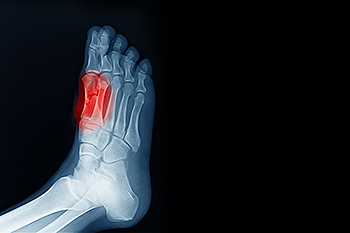

To figure out the cause of foot pain, podiatrists utilize several different methods. This can range from simple visual inspections and sensation tests to X-rays and MRI scans. Prior medical history, family medical history, and any recent physical traumatic events will all be taken into consideration for a proper diagnosis.